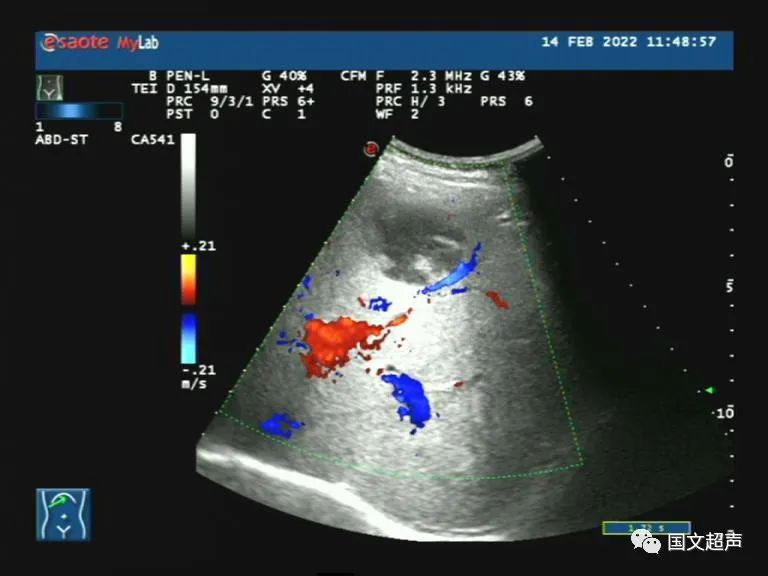

超聲檢查:右側(cè)髂肌、髂腰肌淺層及前方探及不均質(zhì)低回聲,形態(tài)不規(guī)則,邊界不清晰,CDFI:血流信號(hào)不明顯,向后方延伸至腰方肌及腰大肌之間,周?chē)W(wǎng)膜及脂肪組織增厚。結(jié)合增強(qiáng)CT檢查結(jié)果,考慮血腫,臨床觀察對(duì)癥治療。